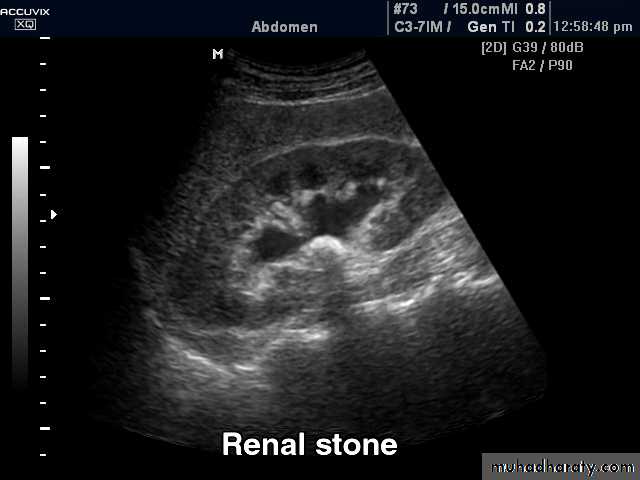

CALCULIMost renal stones are calcified and show varying density on plain x-ray films.

Pure uric acid & xanthine stones are radiolucent on plain radiography, but are well seen at CT or US.

Plain film is more sensitive than US for detecting ureteric calculi.

Stones regardless their composition are intensely echogenic (By U/S) and cast acoustic shadows